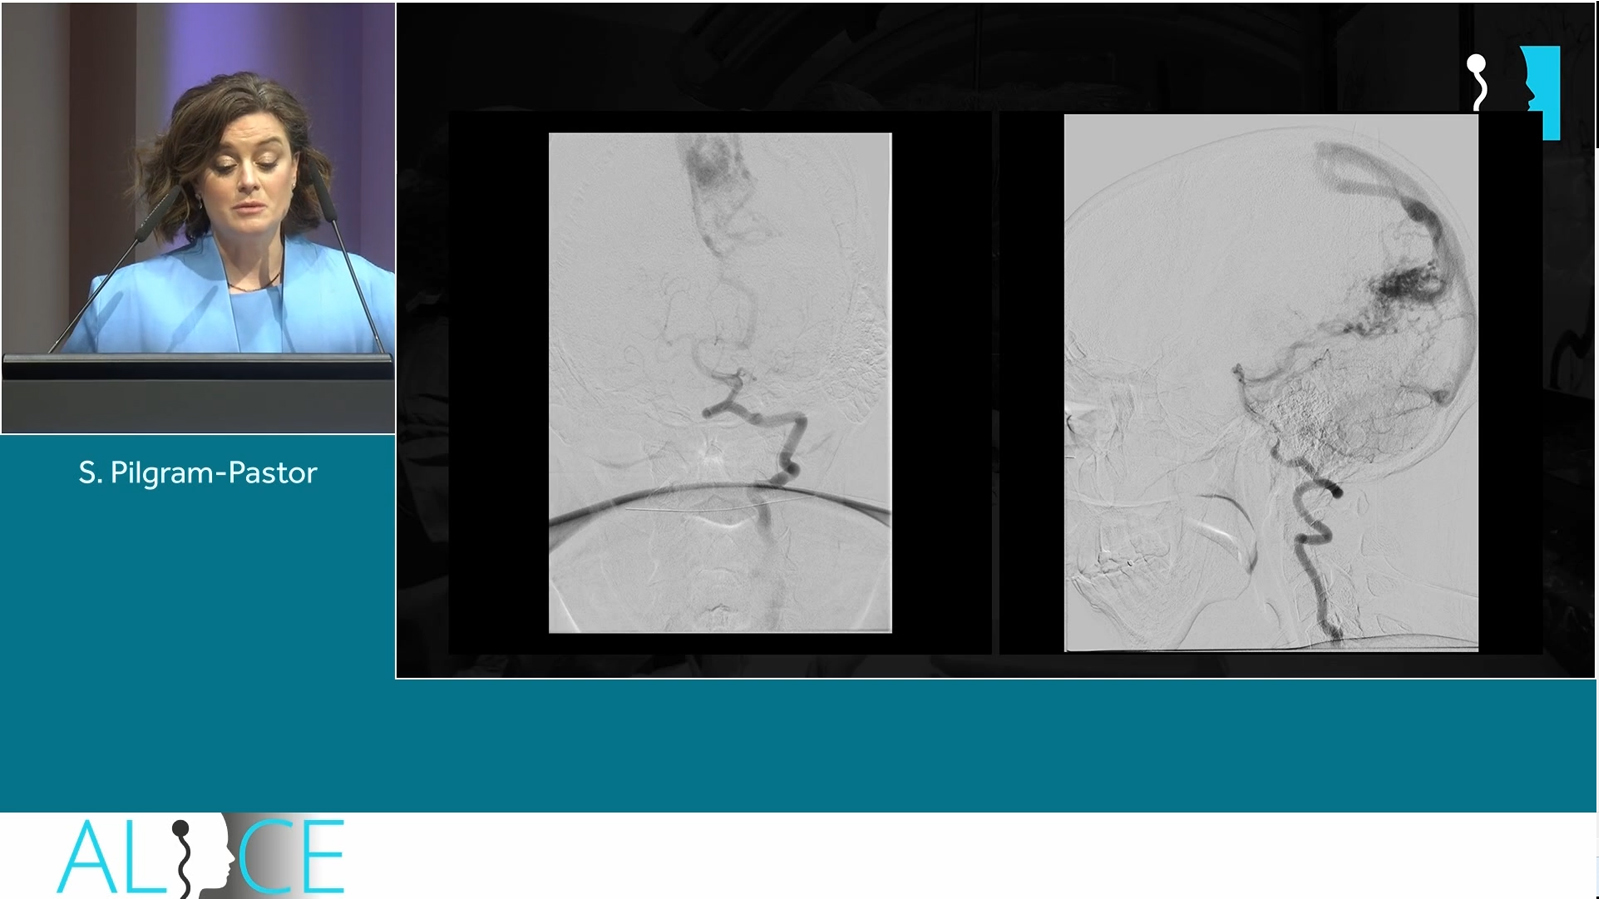

from Bordeaux: a "sequenced" coiling to adress a multilobulated complexe intracranial aneurysm